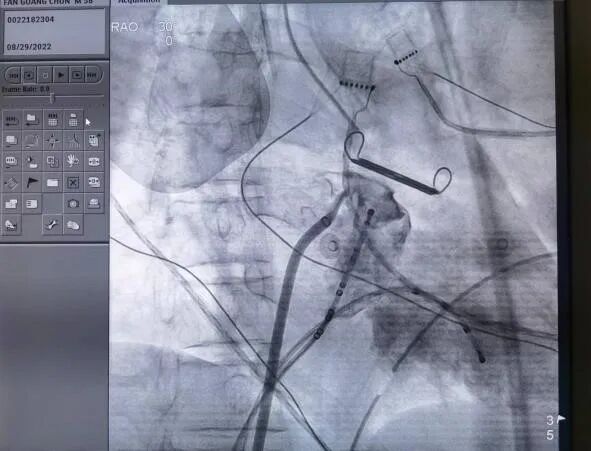

手术直播(十八):经心尖TAVR

术 者:郭惠明、刘健

(广东省人民医院)

今日下午的第三台手术直播来自广东省人民医院心外科郭惠明教授与刘健教授手术团队。患者为76岁男性,反复胸闷伴气促1年、加重2周,强心、利尿治疗效果有限,高血压病史20年。

经胸心脏彩超示:主动脉瓣重度返流,缩流颈8.5mm,返流面积8.1cm²;左心扩大,左室舒张末内径66mm,左室收缩末内径40mm,左房45mm,EF62%。基于心脏CTA的评估显示患者为三叶主动脉瓣且无明显钙化,瓣环周长折算直径24.4mm,左冠开口高度9.8mm,左冠瓣瓣叶长度13.5mm,左髂总动脉瘤。NT-proBNP1991.0pg/ml,肌酐174.57umol/L。心电图、肺通气功能、胸片未见异常。

造影见主动脉瓣大量反流

瓣膜释放前经食道超声

该患者体表面积为1.86m²,STS PROM达8.68%。鉴于患者瓣为纯返流病变,且年龄较高、左冠瓣较长、手术风险大,在与患者及家属充分沟通后,郭惠明教授与刘健教授决定给患者行经心尖TAVR,选用27mm瓣膜。

释放瓣膜

造影确定定位键位置与冠脉情况

再次造影无瓣周漏冠脉显影良好

瓣膜释放后食道超声

经DSA透视下定位心尖位置,主刀团队于左腋前线第五肋间做一3.5cm水平切口,从穿刺心尖至退出植入系统、荷包打结仅耗时不到10分钟,整台手术耗时仅56分钟,再次造影及复做经食道心超见瓣膜位置满意,无明显瓣周漏及瓣内返流、左右冠脉显影良好,心尖切口荷包无出血,在做到微创、高效的同时,实现了满意的手术效果。